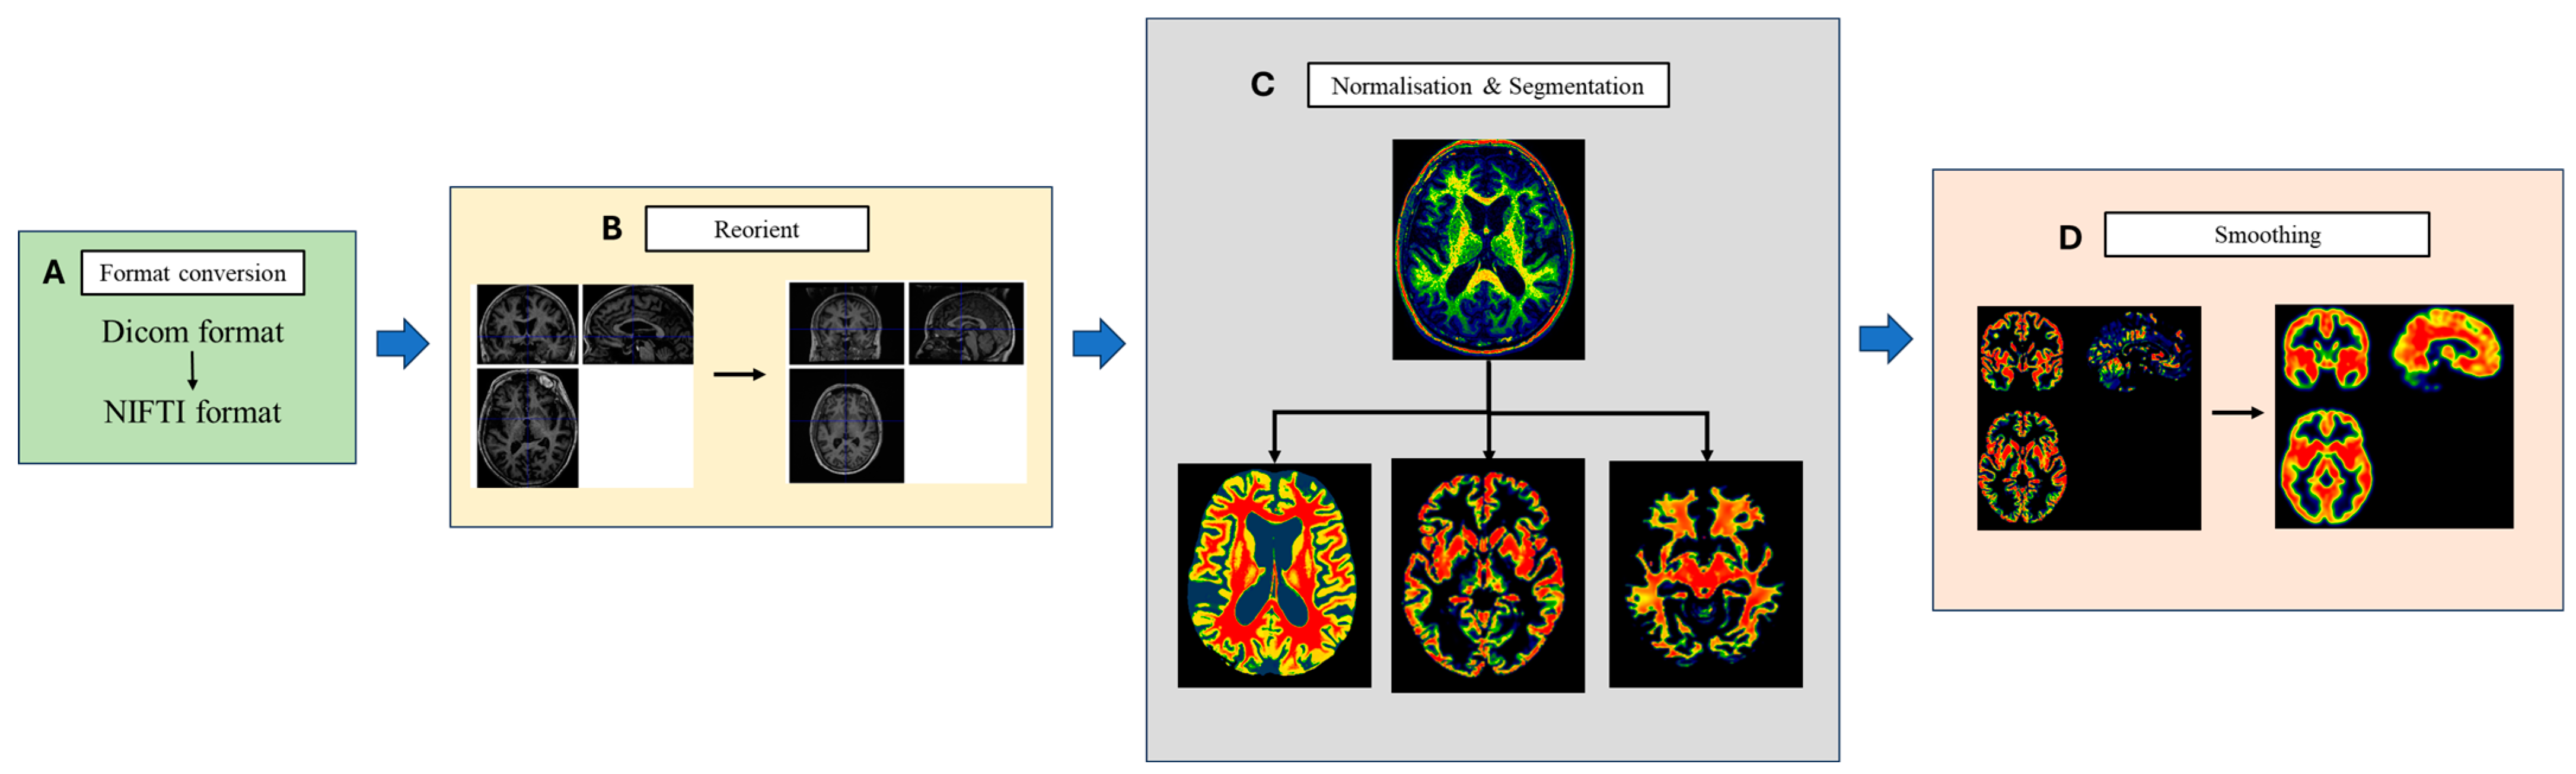

2.5.2. High-Resolution 3D-T1WI Image